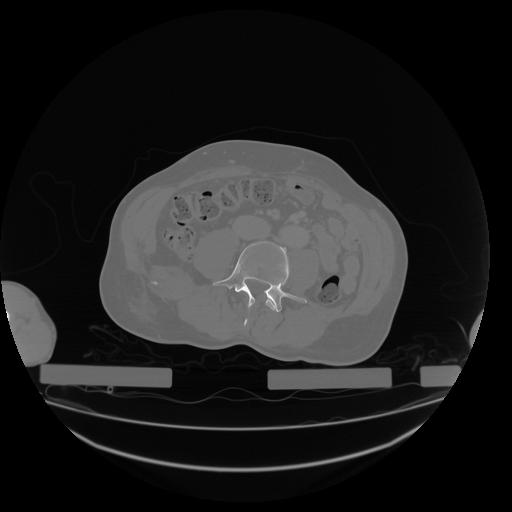

34 CUERPO,CE,Vol,1.0,CUERPO,,